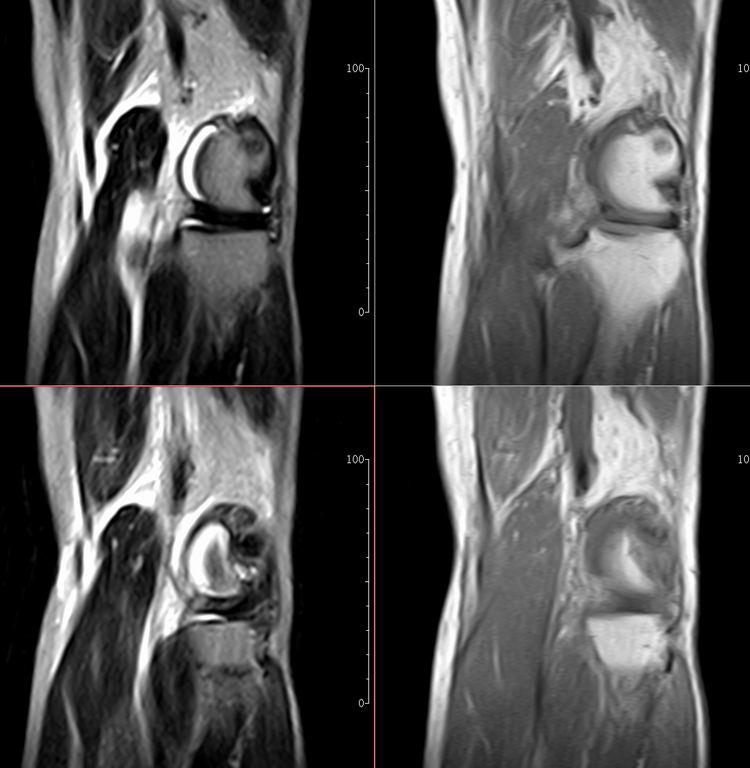

标题: MRI1910:M 687Y。近日因外伤疼痛,而就诊。

m 687y。近日因外伤疼痛,而就诊。有外侧副韧带损伤吗??因片子较差各位请包涵。

有韧带损伤

关节退行性变伴股骨外髁关节面下囊肿,不除外剥脱性骨软骨炎.关节积液,髌骨软化症

体位不标准。关节退变伴关节积液。

1)膝关节骨质退行性改变。

2)由于体位的关系不能确定有外侧副韧带的损伤。

关节退变伴关节积液,外侧副韧带的损伤

关节积液,外侧副韧带的损伤